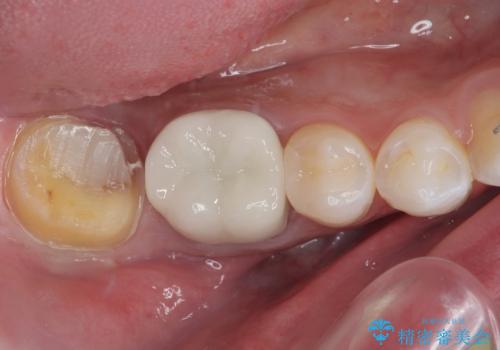

- 歯列矯正後の後戻りのチェックで来院された際に右下に虫歯ができて歯に穴が開いたとのことで来院された患者様です。

レントゲン撮影を行い、歯髄診査を行いました。歯髄の正常な反応を確認できたのでオールセラミッククラウンによる虫歯治療をすることにしました。

虫歯の上に歯茎が覆いかぶさっていたので、レーザーにて歯茎を除去し虫歯が大きいことが予想できたのでラバーダム防湿下で虫歯の除去をしました。

オールセラミッククラウンに適した形に整え、歯と歯茎の間に圧排糸と言われる糸を入れてシリコーン印象材にて型どりをしました。